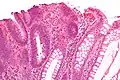

| Adénome tubulaire (villositaire, tubulovilleux) | Glandes tubulaires avec des noyaux allongés (au moins à faible teneur atypie) | Oui | ![]() |

||